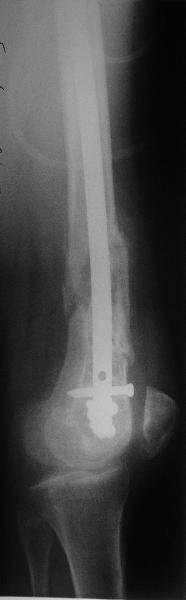

Антеградный остеосинтез при дистальных переломах бедра мы применяем давно, этот материал обобщен в канд. диссертации Александра Виноградского.

Предприятие ЦИТО выпускает доработанные нами гвозди, которые хорошо годятся для дистальных переломов, да и недороги. Можно вводть в дистальное овальное отверстие 3 винта, которые заклинивают друг друга.

Большеберцовые стержни отлично выполняют роль ретроградных бедренных. Конечно, которые не 9, а 12 мм в диаметре.

Примеры приложены.